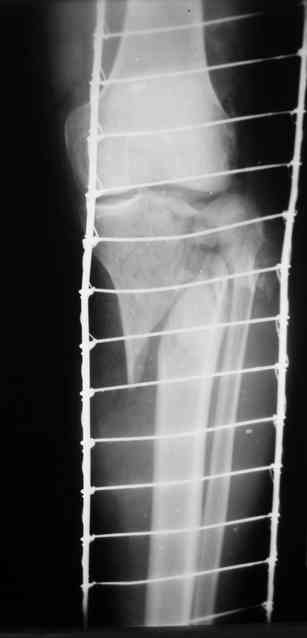

Р-граммы и фото за 4.05.2007 - 7-е сутки после операции.

Ход операции - линейным разрезом по передней поверхности голени обнажена зона ложного сустава большеберцовой кости. От кости отсепарованы медиально м/ткани. Из зоны ложного сустава убраны рубцовые ткани, мобилизован дистальный отломок. По передней поверхности удалены два осколка, связанных грануляциями. Произведено удаление грануляционной ткани из проксимального отломка (на вид сине-серого цвета), "чистого" гноя не было. Затем произведено наложение аппарата и репозиция отломков. По передне-медиальной поверхности образовался дефект до 4х2х2 см + полость в проксимальном отломке. Удаленные осколки очищены от грануляций, уложены в место дефекта, зажаты между отломками. После иссечения раны по передней поверхности, находящейся рядом с операционной раной, последняя ушита с большим натяжением.

Перелом мыщелка сросся. Проксимальный отломок очень порозный.

Аппарат видел, репозиции не заметил. О "наложенном" аппарате: спицы в проксимальном отломке б\берцовой кости проведены очень низко, и опять только две, как и в первом аппарате. Почему только одна спица в дистальном парафрактурном кольце? Проксимальная база на бедре должна улучшить стабильность проксимального фрагмента tibia? Ничего подобного двумя спицами в одной базе при таком длинном рычаге вы не добьетесь, а вот совсем потерять движения в коленном суставе они почти гарантируют.

О репозиции: мыщелок сросся и слава Богу, но основные отломки фиксированы в вальгусном положении, собственно как и было, это критично. В чем состояла репозиция?

Согласен с оценкой Алексея. Секцию на бедро не нужно, на ровном месте сформируется контрактура коленного сустава. В проксимальный эпиметафиза большеберцовой ввели бы 4-5 спиц с упорами, в том числе в виде петли, и хватило бы.

Кольцо с бедра демонтировать. Добавить кольцо проксимальней к коленному суставу с двумя спицами. Соединить с нижним предварительно проведя еще одну спицу в этом кольце. Получится проксимальный модуль.

Провести еще одну спицу в проксимальном кольце дистального модуля. Между ними (модулями) убрать штанги ... "через колено" устранить варус и зафиксировать тремя резьбовыми штангами.